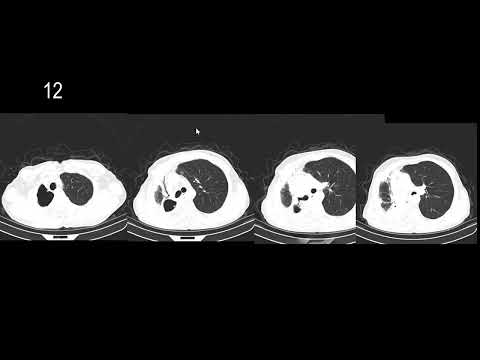

An educational youtube channel dedicated to Neuroradiology. My name is Sven. I'm a 42-year old Neuroradiologist from Belgium and I love teaching and I love neuroradiology. This channel combines both these passions. My teaching is philosophy is "try to keep it simple" and "I wish someone would have told me this when I was a resident". I work in a teaching hospital and I want to teach my assistants / registrars / residents as much as i can during the short time they rotate at out department. I try to do the same in these videos. I'm always open to feedback and constructive criticism. I'm not perfect and neither are these videos. If you have any comments, questions or feedback, just let me know. If you have any requests for future videos, I'm always open to suggestions. Hope you enjoy this channel. If you're here, it means you're passionate about Neuroradiology. I hope these videos only strenghten that passion :). Kind regards, Sven